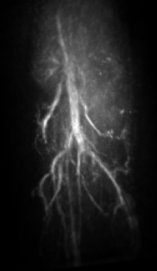

V.3 Experimental results

The maximum intensity projection (MIP) of the 3D mouse images reconstructed by use of the GPU-based implementations reveal the mouse body vasculature as shown in Fig. 7. Images reconstructed by use of both the PLS-Int and the PLS-Sph algorithms appear to have cleaner background than do the images reconstructed by use of the FBP algorithm from the same amount of data. All images reconstructed by iterative algorithms were obtained by 202020-iterations starting with uniform zeros as the initial guess. The PLS-Int algorithm took approximately a half day and 222 days to process the “quarter data” and the “full data” respectively. The PLS-Sph algorithm took approximately one day and 444 days to process the “quarter data” and the “full data” respectively. Alternatively, if the CPU-based implementations were utilized, the PLS-Int algorithm would take an estimated 686868 days and 277277277 days to process the “quarter data” and the “full data” respectively. The PLS-Sph algorithm would take an estimated 275275275 days and 1,10011001,100 days to process the “quarter data” and the “full data” respectively.